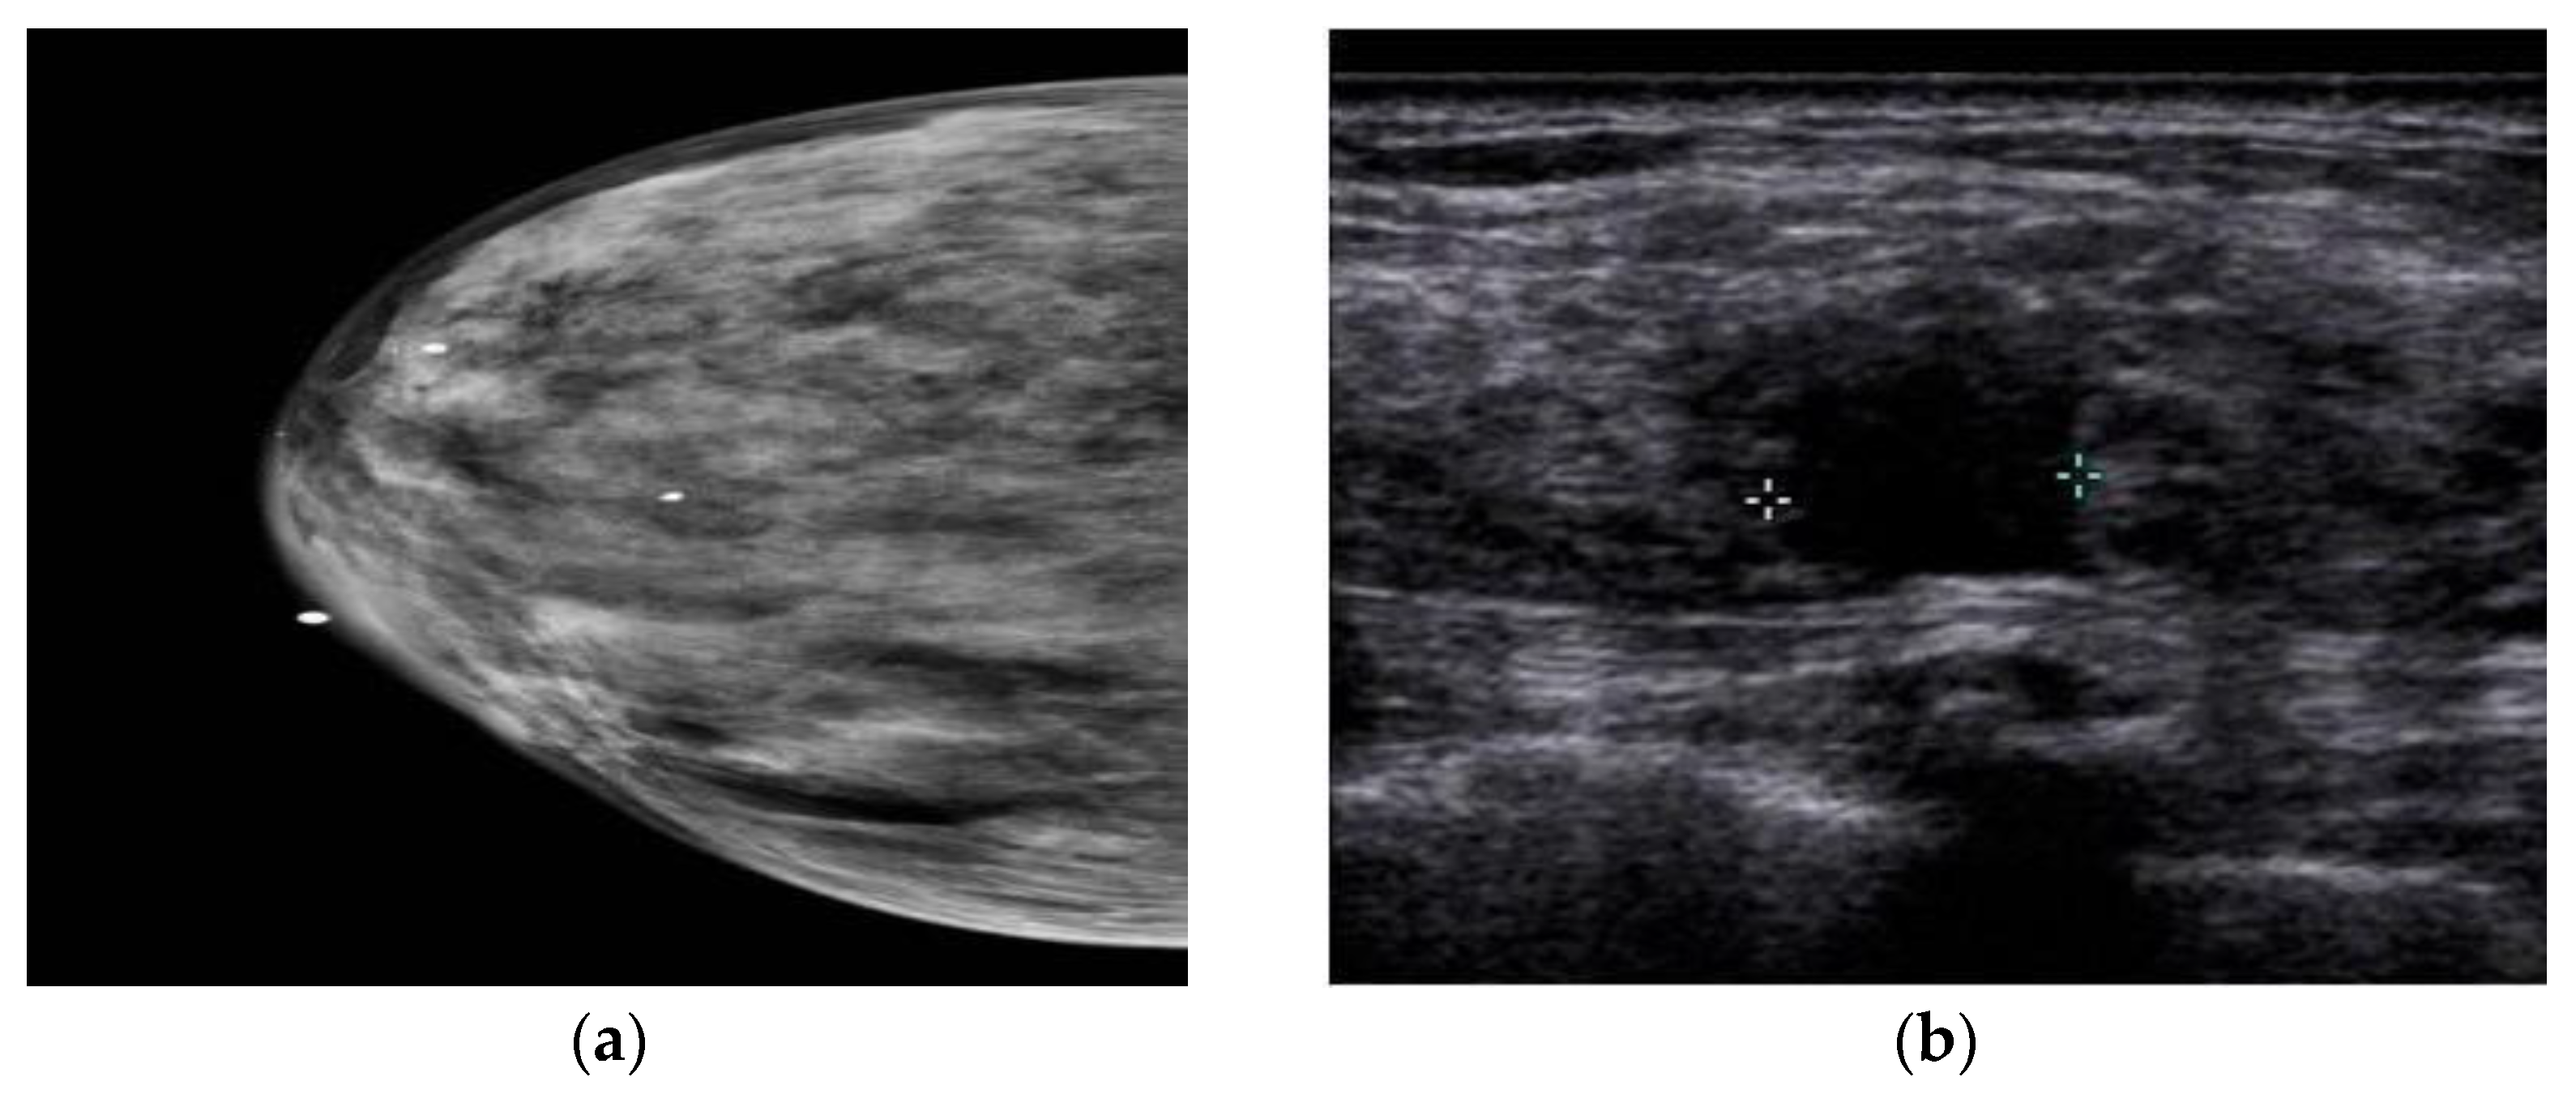

3. Ultrasound Imaging (US)

- Choudhery, S.; Axmacher, J.; Conners, A.L.; Geske, J.; Brandt, K. Masses in the era of screening tomosynthesis: Is diagnostic ultrasound sufficient? Br. J. Radiol. 2019, 92, 20180801. [Google Scholar] [CrossRef]

- Vourtsis, A.; Kachulis, A. The performance of 3D ABUS versus HHUS in the visualisation and BI-RADS characterisation of breast lesions in a large cohort of 1886 women. Eur. Radiol. 2018, 28, 592–601. [Google Scholar] [CrossRef]

- Lin, X.; Wang, J.; Han, F.; Fu, J.; Li, A. Analysis of eighty-one cases with breast lesions using automated breast volume scanner and comparison with handheld ultrasound. Eur. J. Radiol. 2012, 81, 873–878. [Google Scholar] [CrossRef]

- Shin, H.J.; Kim, H.H.; Cha, J.H. Current status of automated breast ultrasonography. Ultrasonography 2015, 34, 165. [Google Scholar] [CrossRef] [PubMed]

- Melnikow, J.; Fenton, J.J.; Whitlock, E.P.; Miglioretti, D.L.; Weyrich, M.S.; Thompson, J.H.; Shah, K. Supplemental Screening for Breast Cancer in Women With Dense Breasts: A Systematic Review for the U.S. Preventive Services Task Force. Ann. Intern. Med. 2016, 164, 268–278. [Google Scholar] [CrossRef] [PubMed]

- Lee, J.M.; Partridge, S.C.; Liao, G.J.; Hippe, D.S.; Kim, A.E.; Lee, C.I.; Rahbar, H.; Scheel, J.R.; Lehman, C.D. Double reading of automated breast ultrasound with digital mammography or digital breast tomosynthesis for breast cancer screening. Clin. Imaging 2019, 55, 119–125. [Google Scholar] [CrossRef] [PubMed]

- Sood, R.; Rositch, A.F.; Shakoor, D.; Ambinder, E.; Pool, K.-L.; Pollack, E.; Mollura, D.J.; Mullen, L.A.; Harvey, S.C. Ultrasound for breast cancer detection globally: A systematic review and meta-analysis. J. Glob. Oncol. 2019, 5, 1–17. [Google Scholar] [CrossRef] [PubMed]